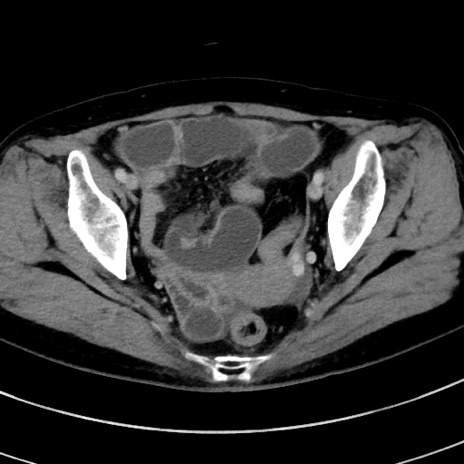

症例9(横断像)

【症例】 60歳代女性

【主訴】むかつき、みぞおちの痛み

【現病歴】3日前よりむかつきがあり、食事がとれない。

【既往歴】糖尿病

【身体所見】発熱なし、心窩部圧痛軽度あるも、腹膜刺激症状なし。

【データ】WBC 7400、CRP 1.92